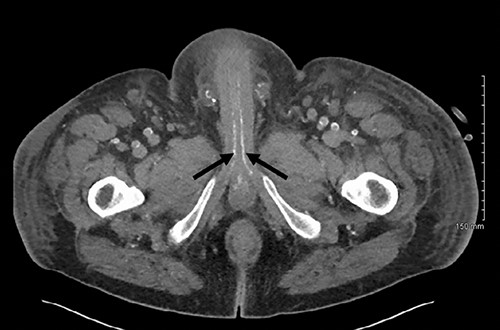

Post-operatively the patient was experiencing ongoing severe penile, examination of the glans was not possible due to oedema and pain. Our patient underwent dialysis to offload excess fluid. A CT angiogram revealed extensive peripheral vascular arterial calcification, including calcification of the internal pudendal and cavernosal arteries (Figs 2 and 3). The inguinal lymphadenopathy was shown to be reactive.

Axial slice of a non-contrast CT AP with arrows delineating calcified cavernosal arteries.

The gold standard for the diagnosis remains skin biopsy. Biopsy of the foreskin at the time of dorsal slit did not elucidate any calciphylaxis, however did out rule malignancy. Glansectomy and circumcision confirmed calciphylaxis with vessel calcification and necrosis. However, often times diagnosis is made based on presentation, bloods and imaging, due to the risk of biopsy potentiating infection. Radiological investigations can aid diagnosis. CT is the most sensitive, assessing the extent of vascular calcification, as in our case [1] (Figs 2 and 3).